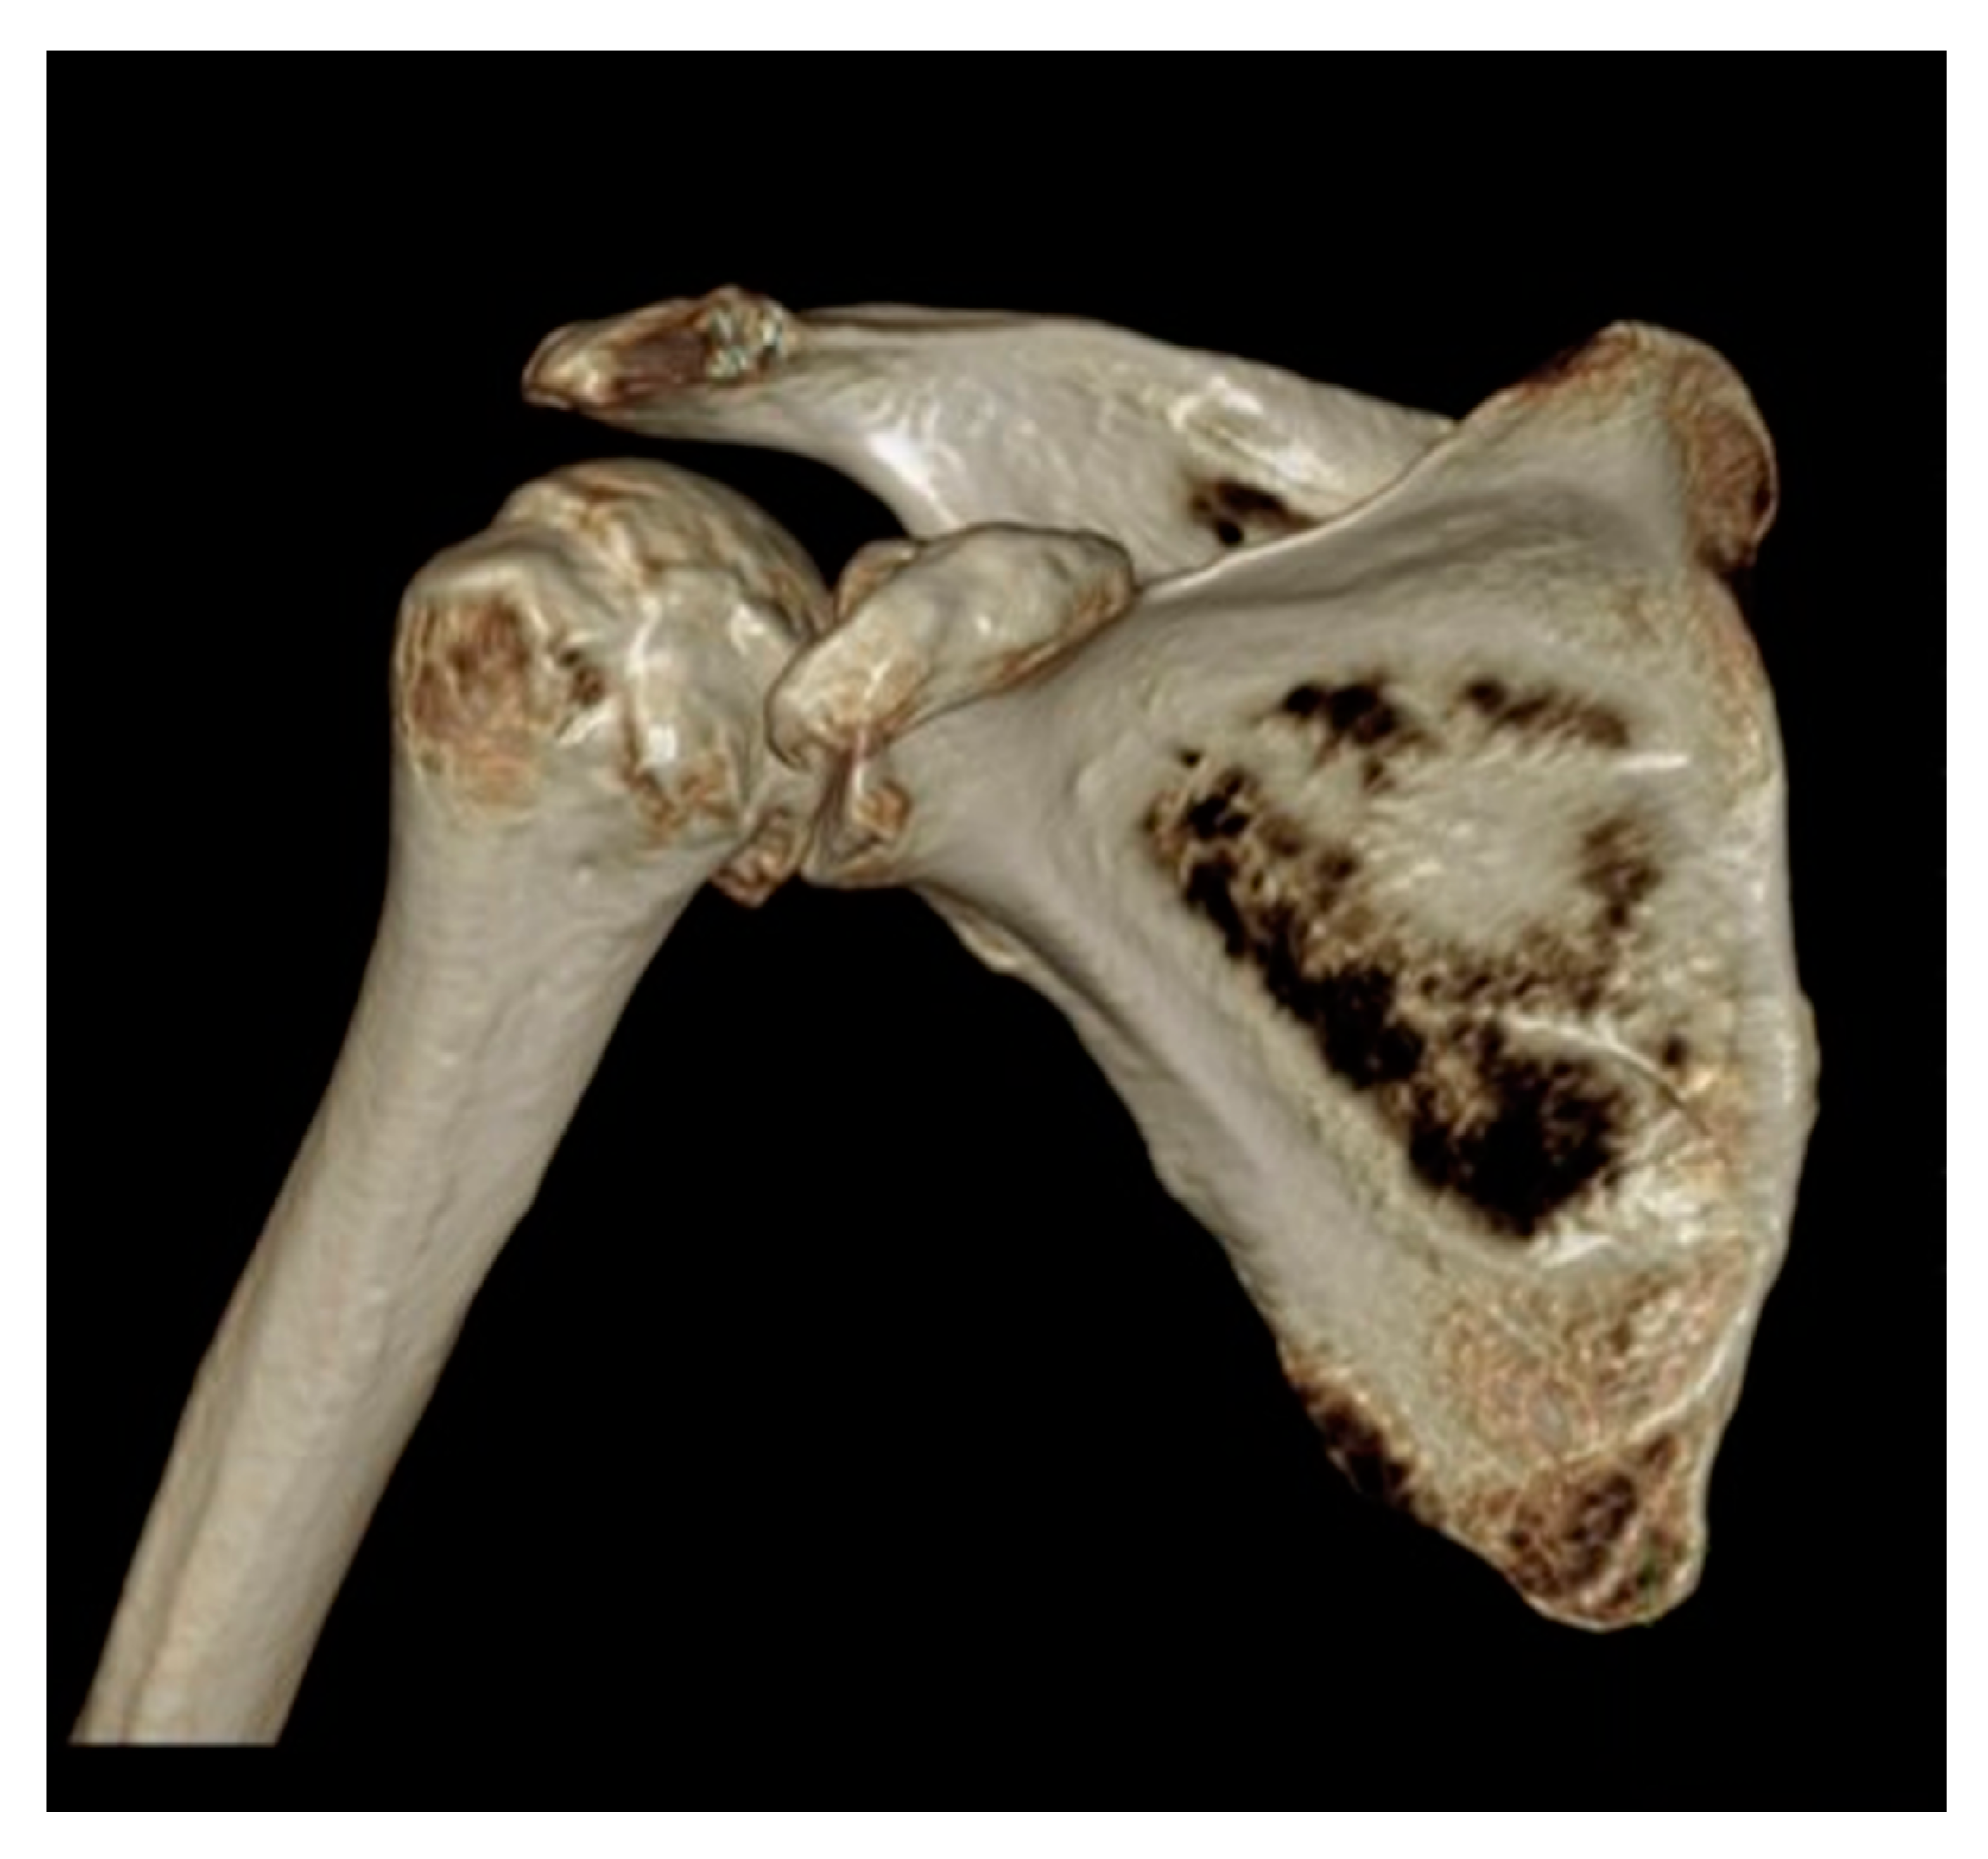

3. Preoperative Imaging

- Walch, G.; Badet, R.; Boulahia, A.; Khoury, A. Morphologic study of the Glenoid in primary glenohumeral osteoarthritis. J. Arthroplast. 1999, 14, 756–760. [Google Scholar] [CrossRef] [PubMed]

- Bercik, M.J.; Kruse, K., 2nd; Yalizis, M.; Gauci, M.-O.; Chaoui, J.; Walch, G. A modification to the Walch classification of the glenoid in primary glenohumeral osteoarthritis using three-dimensional imaging. J. Shoulder Elb. Surg. 2016, 25, 1601–1606. [Google Scholar] [CrossRef]

- Budge, M.D.; Lewis, G.S.; Schaefer, E.; Coquia, S.; Flemming, D.J.; Armstrong, A.D. Comparison of standard two-dimensional and three-dimensional corrected glenoid version measurements. J. Shoulder Elb. Surg. 2011, 20, 577–583. [Google Scholar] [CrossRef]